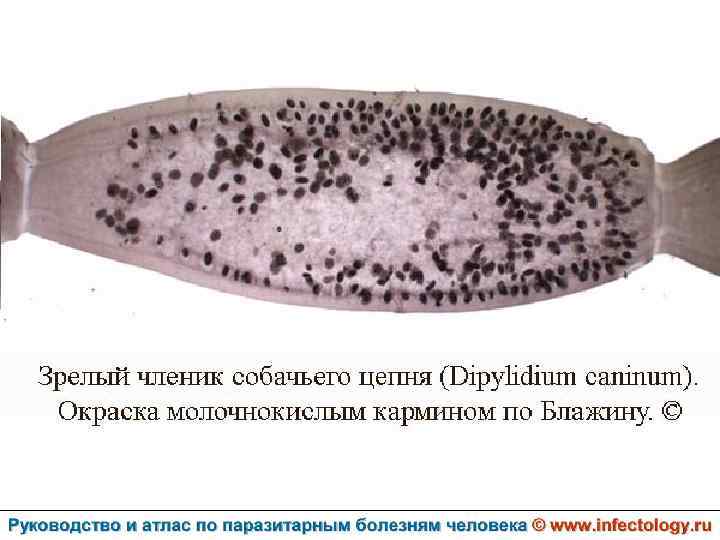

Дипилидиоз (шифр по МКБ 10 – B 71. 1) зоонозный биогельминтоз, характеризующийся аллергизацией организма и нарушением функций пищеварительного тракта.